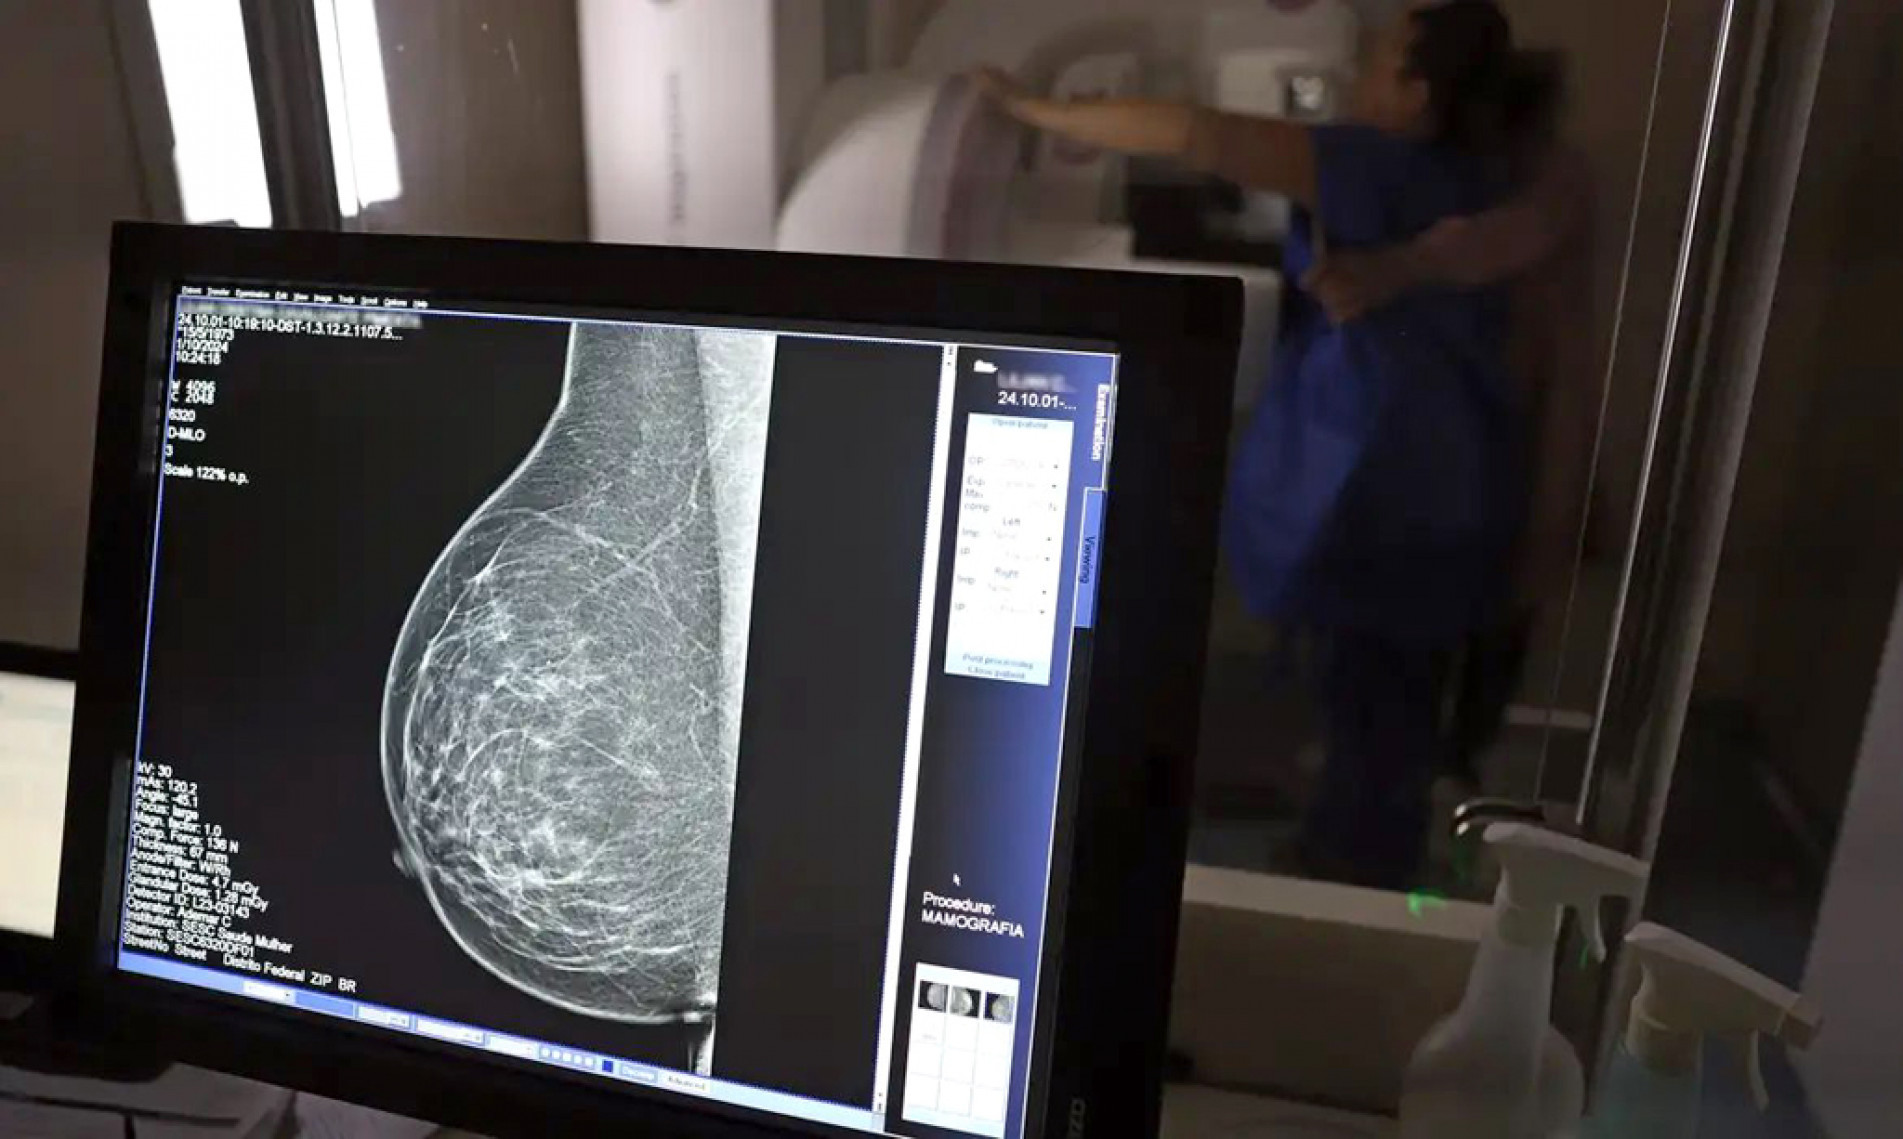

Antes, orientação era a partir dos 50 anos (Crédito: JOSÉ CRUZ / ARQUIVO ABR)

O Ministério da Saúde passou a recomendar o acesso a mamografia, via Sistema Único de Saúde (SUS), para mulheres de 40 a 49 anos — mesmo que não haja sinais ou sintomas de câncer de mama. De acordo com a pasta, a faixa etária concentra 23% dos casos da doença, e a detecção precoce aumenta as chances de cura. Até então, a orientação era que o exame fosse feito a partir dos 50 anos.

A medida faz parte de um conjunto de ações anunciadas ontem (23), voltado para a melhoria do diagnóstico e da assistência. A recomendação para mulheres a partir dos 40 anos é que o exame seja feito sob demanda, em decisão conjunta com o profissional de saúde. (Agência Brasil)